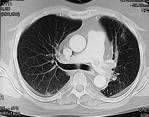

January 4, 2010 - Computed tomography (CT) is the overwhelmingly preferred technique of emergency physicians and radiologists for the diagnosis of pulmonary embolism (PE), according to a study in the January issue of the American Journal of Roentgenology.

The main diagnostic imaging tests available to diagnose PE are CT, lung scintigraphy, and MRI. In the study, led by Saurabh Jha, M.D., researchers set out to assess the diagnostic approach to PE practiced by emergency physicians and recommended by radiologists.

The results found that emergency physicians nearly uniformly (96 percent) chose CT as the preferred first-line investigation because of accuracy, overall access to CT, 24-hour interpretation, and capability for alternative diagnosis. Ninety percent of radiologists also said CT was the first-line medical imaging technique for excluding pulmonary embolism.

Although, approaches differed on the use of CT for pregnant patients, Dr. Jha said noted that CT is the nearly universal first-line imaging choice for the diagnosis of PE.